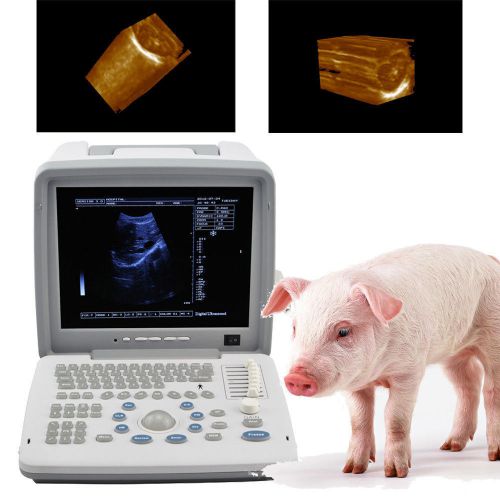

Veterinary VET 3D Full Digital Portable Ultrasound Scanner convex 3D workstation

External 3D Veterinary VET Full Digital Portable Ultrasound Scanner Micro convex

Vet Veterinary Wrist Held Ultrasound Scanner w Probe for Small and Large Animal

12.1 Veterinary VET Full Digital Portable Ultrasound Scanner linear 3D software

Veterinary vet Full Digital Portable Ultrasound Scanner Rectal 3D workstation

2014 Veterinary vet Full Digital Portable Ultrasound Scanner Rectal 3D Software